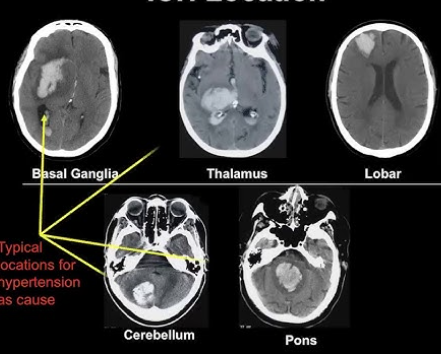

What is Intraparenchymal haemorrhage, and what does it look like on CT head?

Intraparenchymal haemorrhage: Blood collection in brain tissue

CT finding: Hyperdense lesions in cerebral hemispheres/brainstem/cerebellum/basal ganglia